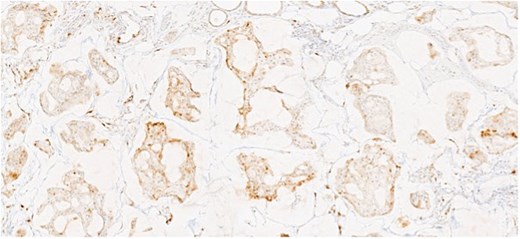

Herein, we present a 75-year-old man who, having been referred to our service with an inguinal hernia, raised concern about a palpable mass present in his right axilla. The main differential on initial examination was that of a simple epidermoid cyst, and consent was obtained for its removal during his elective hernia repair. Subsequent histology however, revealed a well differentiated MAC. There was extensive involvement of the deep and superficial reticular dermis (Figs 1and 2). Lymphovascular invasion was present. Sweat glands were focally involved by the carcinoma. The differential diagnosis included PCMC and metastasis from other primary sites of MAC such as breast, lung and gastrointestinal. Immunohistochemical profiling was performed on the specimen. CK 7, HER2 (4B5, 3+), GATA3 (strong, diffuse), and P16 (focal, weak) were positive (Figs 3–6). SOX10, CK 20, CDX2, TTF-1, p40, ER, and PR were negative which supported the diagnosis of MAC with either breast or PCMC origin based particularly on GATA3 expression.

(a, b) Section of skin showing dermal lesion composed of nests of tumor cells floating in pools of extracellular mucin.

Section showing tumor cells with low to intermediate nuclear grade floating in pools of extracellular mucin separated by fibrous septa.